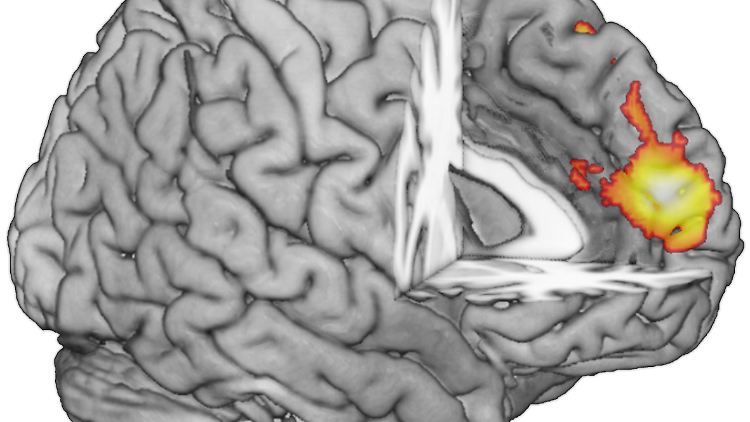

Der dorsomediale Präfrontalkortex (dmPFC) – helle Markierung – liegt im Stirnbereich des Gehirns.

(Foto: Forschungszentrum Jülich)

Urteil über Stimmen und Gesichter

In der Untersuchung haben 44 gesunde Erwachsene verschiedene Stimmen zu hören bekommen, die sie auf ihre Attraktivität und Vertrauenswürdigkeit hin einschätzen sollten. Dabei lagen die Probanden in einem Magnetresonanztomographen (MRT), mit dessen Hilfe die Gehirnaktivität sichtbar gemacht werden konnte. Während die Entscheidung gefällt wurde, war jedes Mal der sogenannte dorsomediale Präfrontalkortext (dmPFC) im vorderen Bereich des Gehirns aktiv. Derselbe Teil, der bei dem gleichen Versuch mit der Beurteilung von Gesichtern kurz zuvor ausgemacht wurde.